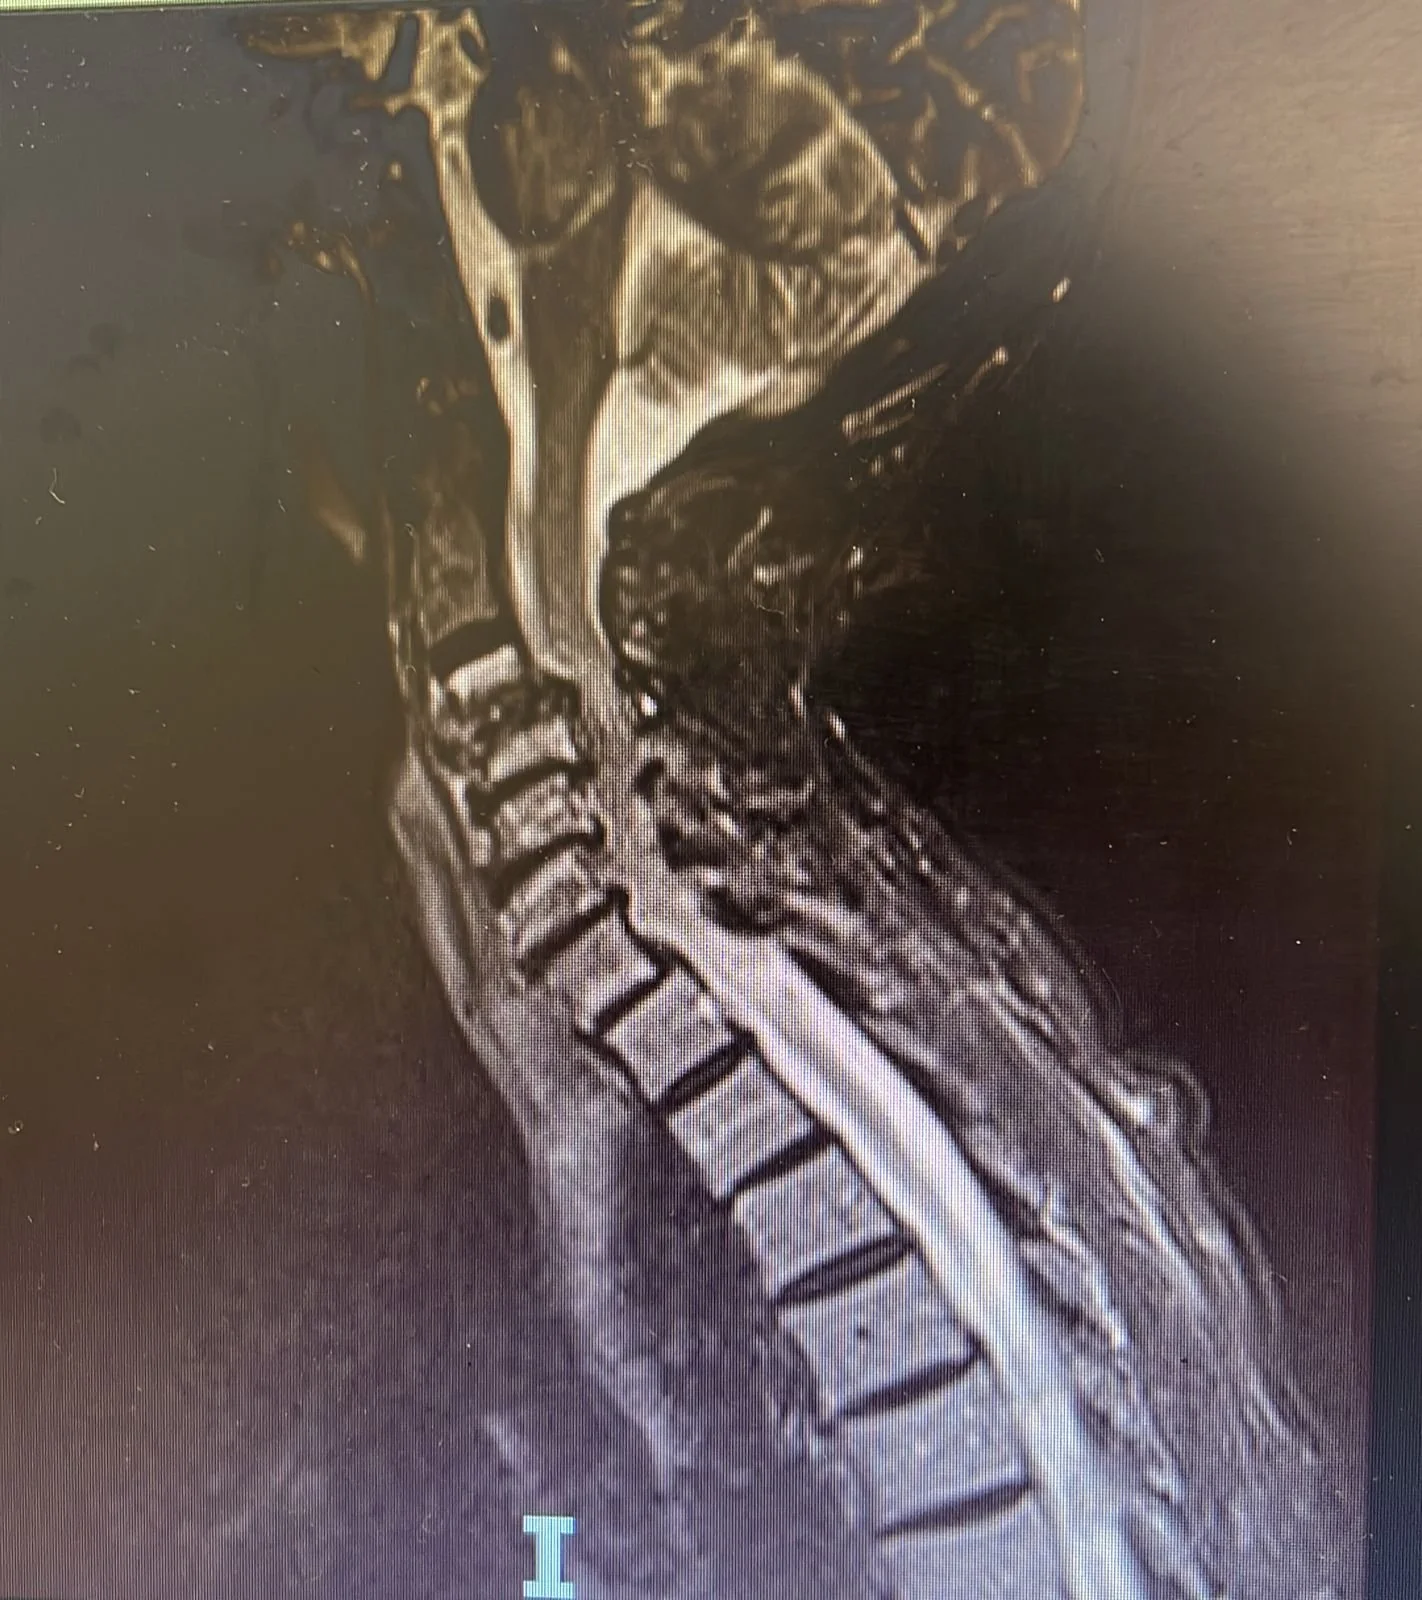

Atendemos patologías como escoliosis, hernias de disco, fracturas vertebrales, y casos complejos de dolor crónico, incluyendo pacientes que han sido operados previamente y continúan con molestias. También tratamos la mielopatía cervical, una condición que afecta significativamente la movilidad y calidad de vida.